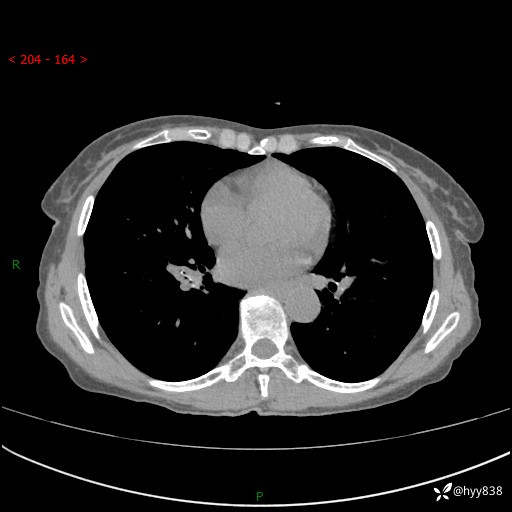

患者性别:男

患者年龄:69岁

简要病史:咳嗽咳痰2月,夜间加重

辅助检查:CT

临床诊断:感染

胸部CT平扫